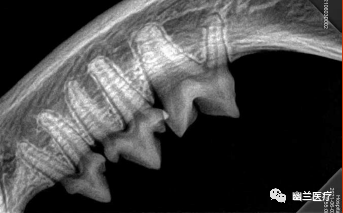

● 牙科DR可用于宠物牙科拍片诊断:牙髓病、牙周病、猫牙吸收等,可以拍摄犬、猫、马等动物,操作简单,安全,可以满足宠物不同的临床需求。

● 图像比普通X光照片更清晰,更易发现病变,从而减少漏诊和误诊。

07

案例分享